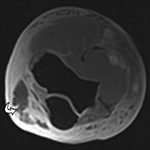

Wraparound Artifact. Axial proton-density-weighted MR image of the right knee demonstrates wraparound artifact (arrow) of the left knee, which is partially imaged (arrowhead).